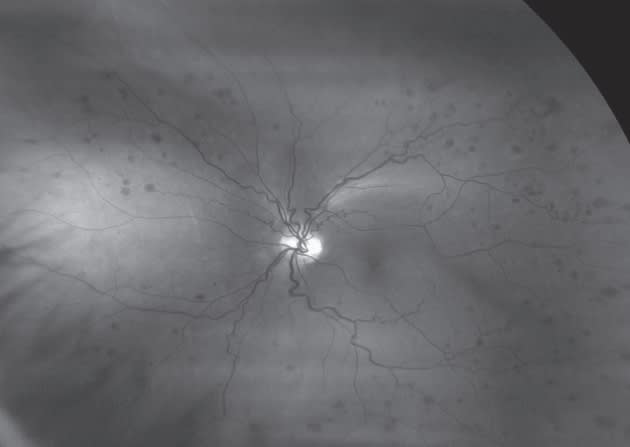

Figure 5. Diabetic retinopathy.

Dr. Nelson: Yes, without question. The ability to view the different wavelength scans separately makes a big difference for detecting small hemorrhages. When I switch to the green laser separation, the hemorrhages light up in black, and it is much easier to see them. With just a quick scan, I can see whether diabetic retinopathy is present throughout the retina.

Dr. Rothschild: I scan all diabetic patients, too. I have seen some beautiful, healthy-looking posterior poles with hemorrhages all around the periphery in diabetic patients.

Dr. Schaeffer: The optomap facilitates precise monitoring and documentation of small peripheral hemorrhages in diabetic patients.